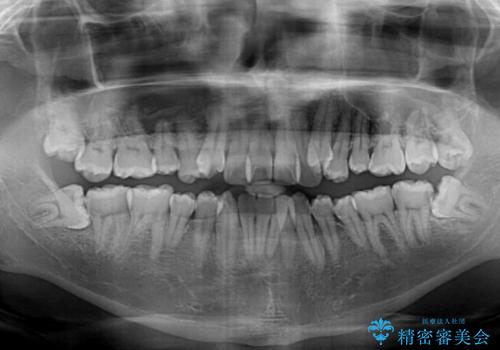

- 八重歯と前歯のクロスバイトを改善したいとのことで来院された患者様です。

マウスピース矯正での自己管理には自信がないとのことで、ワイヤー装置による矯正治療を行うこととしました。

デコボコの程度は強かったのですが、口元の突出感はなかったため、非抜歯矯正としました。